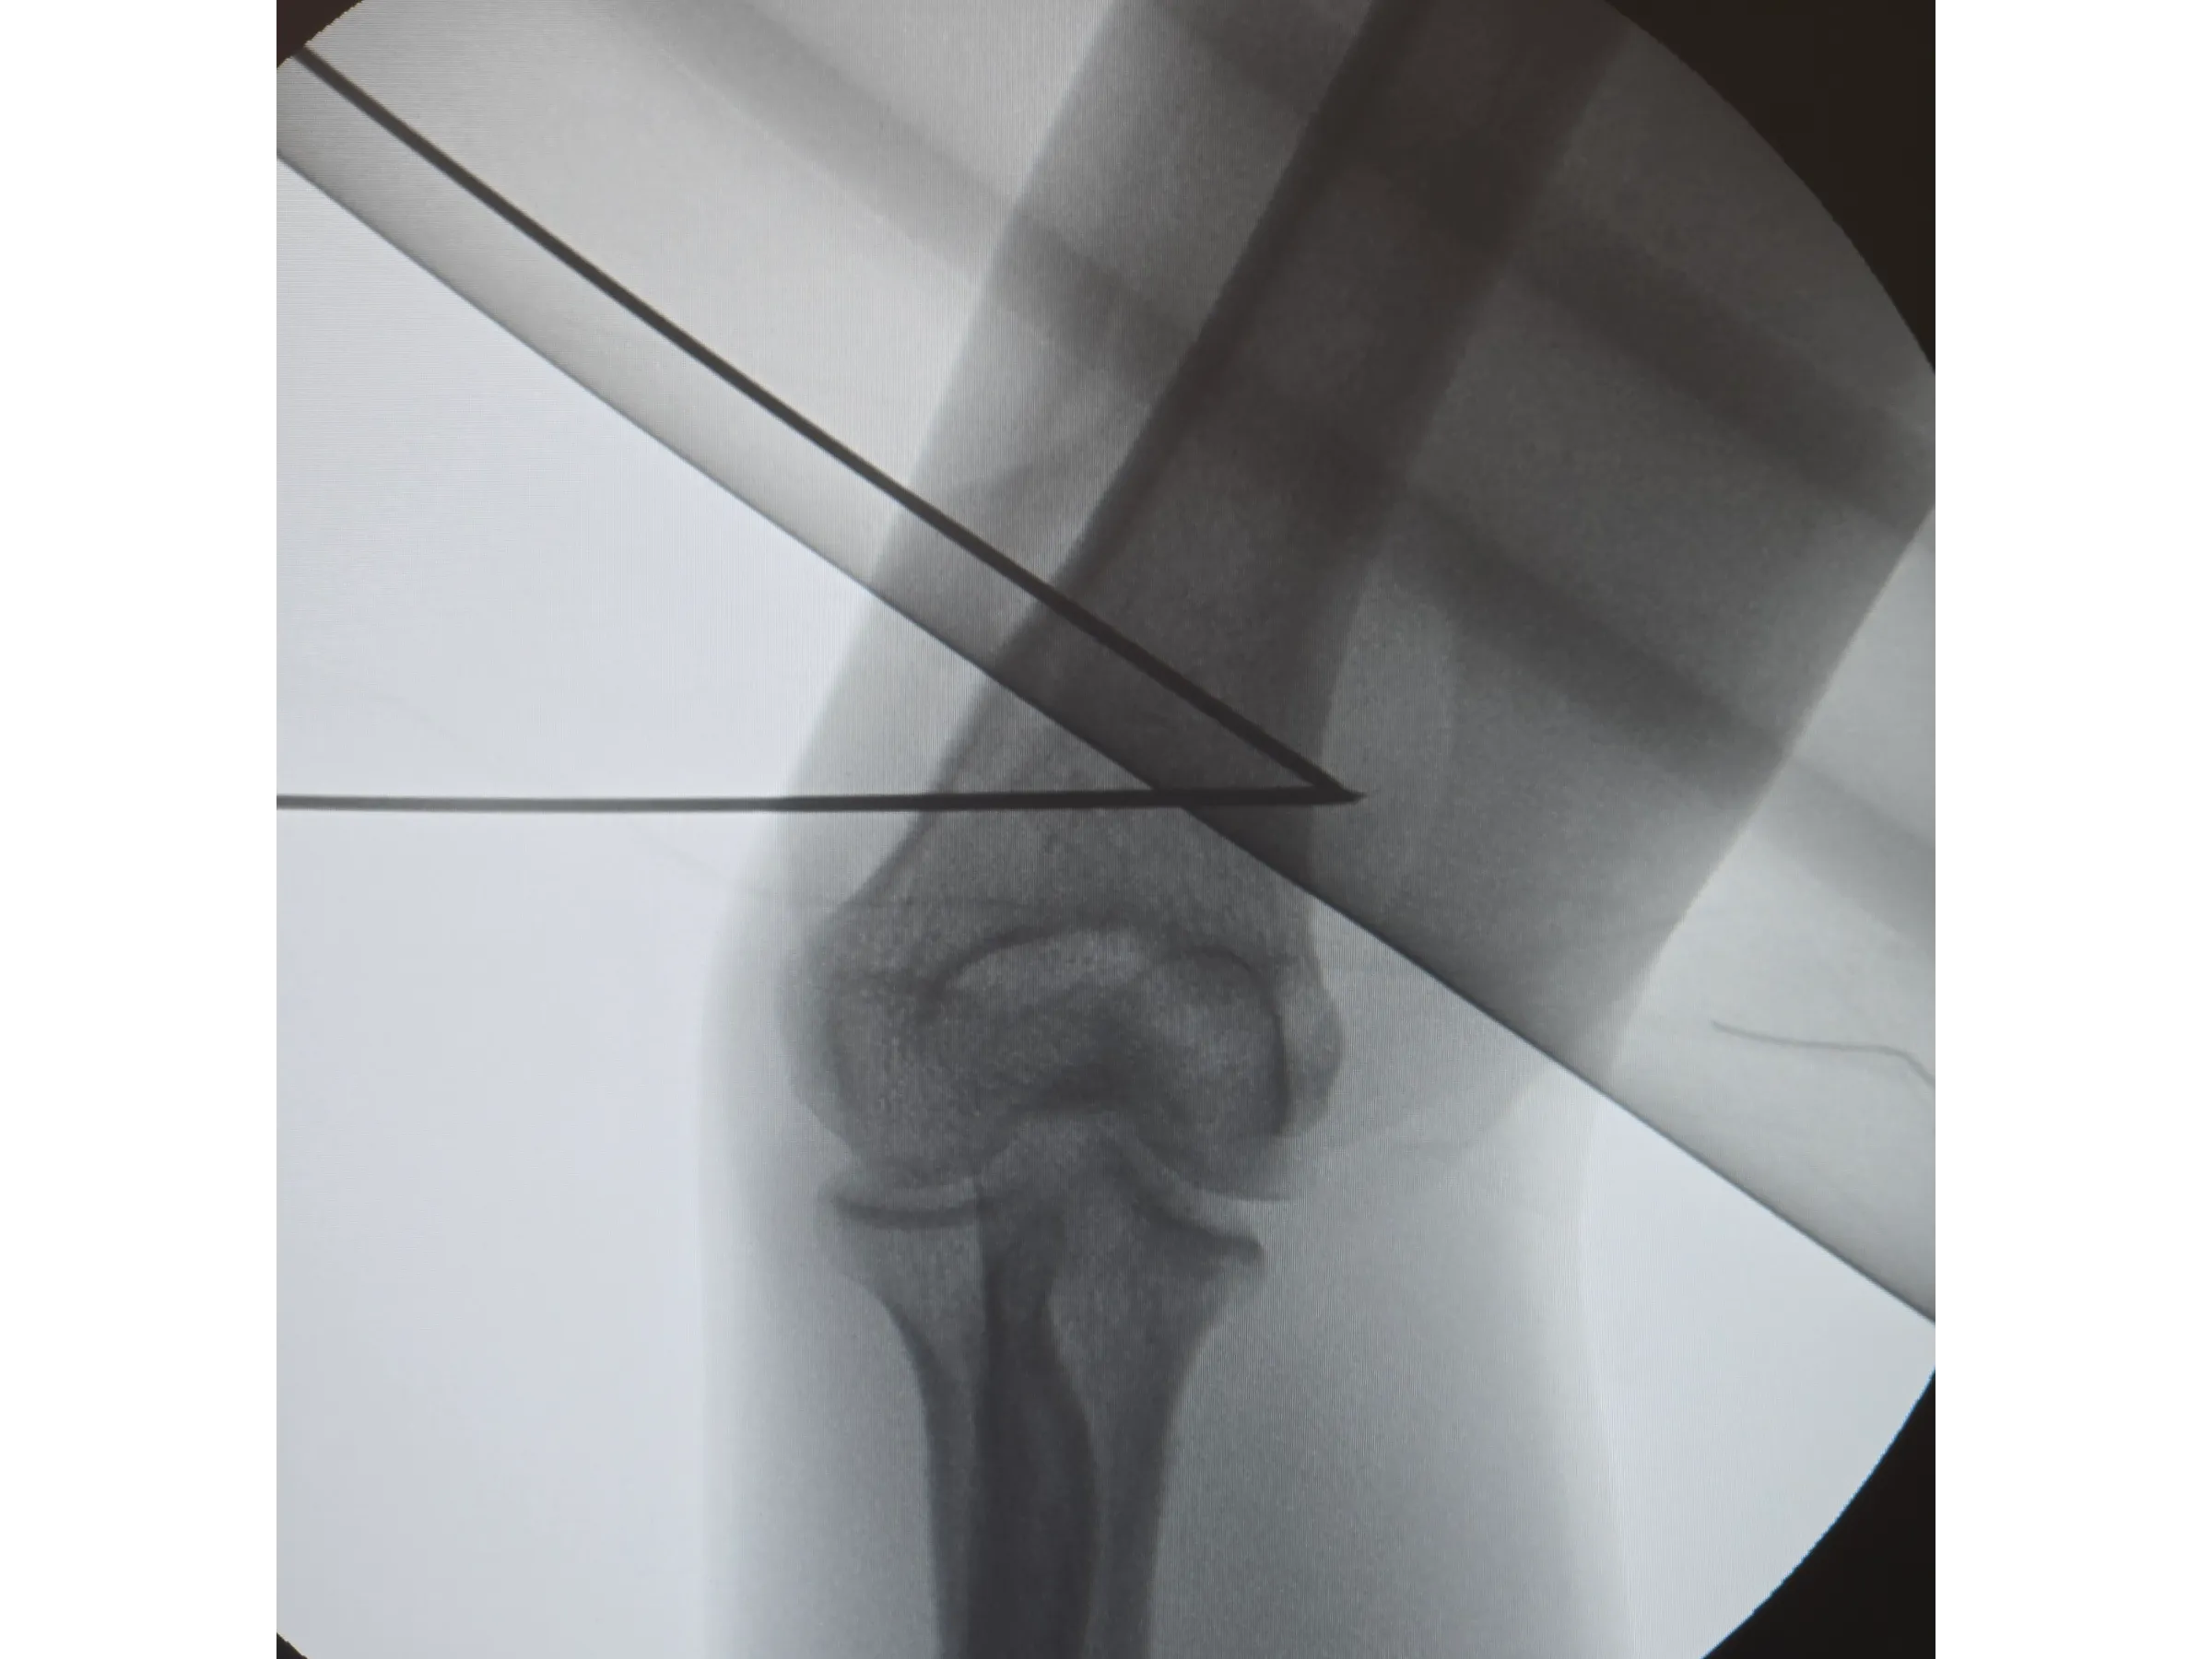

- Planejamento pré-operatório com impressão 3D e gabarito cirúrgico;

- Osteotomia guiada e fixação com placas bloqueadas;

- Osteotomia Guiada: correção angular com alinhamento axial e estabilidade biomecânica;